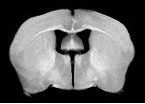

Se utiliza principalmente en medicina para observar alteraciones en los tejidos y detectar cáncer y otras patologías.

MRI Clínico de 3T: Achieva 3,0 T TX de Philips.

- Achieva 3,0 T TX, con tecnología de MultiTransmisión y gestión inteligente de RF.